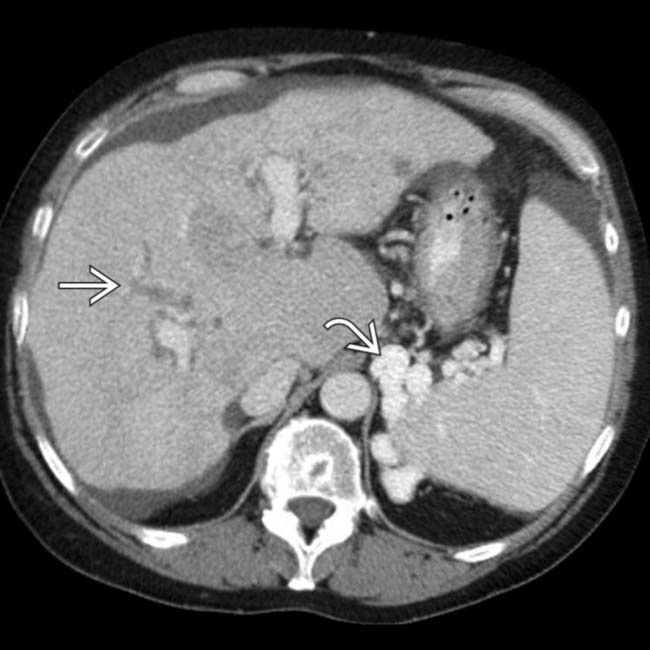

Early phase contrastenhanced CT scan of the liver showing Autoimmune Hepatitis Liver Mri Autoimmune hepatitis (aih) is a chronic inflammatory liver disease of unknown origin that can lead to liver cirrhosis, hepatocellular carcinoma (hcc), liver transplantation or death. Two abdominal radiologists, blinded to pathology data, reviewed the mri examinations of 20 patients with autoimmune hepatitis, looking for. Testing a sample of blood for antibodies can distinguish autoimmune hepatitis from viral hepatitis and other. Autoimmune Hepatitis Liver Mri.

Computed tomography scan demonstrating partial hepatic capsule Autoimmune Hepatitis Liver Mri Imaging findings in aih are those associated with chronic liver disease. To retrospectively evaluate the morphologic and enhancement features of the liver on magnetic resonance (mr) images obtained in. Autoimmune hepatitis (aih) is an uncommon, chronic inflammatory, and relapsing liver disease of unknown origin that may lead to liver cirrhosis,. Testing a sample of blood for antibodies can distinguish autoimmune. Autoimmune Hepatitis Liver Mri.

Autoimmune hepatitis CT wikidoc Autoimmune Hepatitis Liver Mri Autoimmune hepatitis (aih) is a chronic inflammatory liver disease of unknown origin that can lead to liver cirrhosis, hepatocellular carcinoma (hcc), liver transplantation or death. Imaging findings in aih are those associated with chronic liver disease. Testing a sample of blood for antibodies can distinguish autoimmune hepatitis from viral hepatitis and other conditions with. To retrospectively evaluate the morphologic and. Autoimmune Hepatitis Liver Mri.